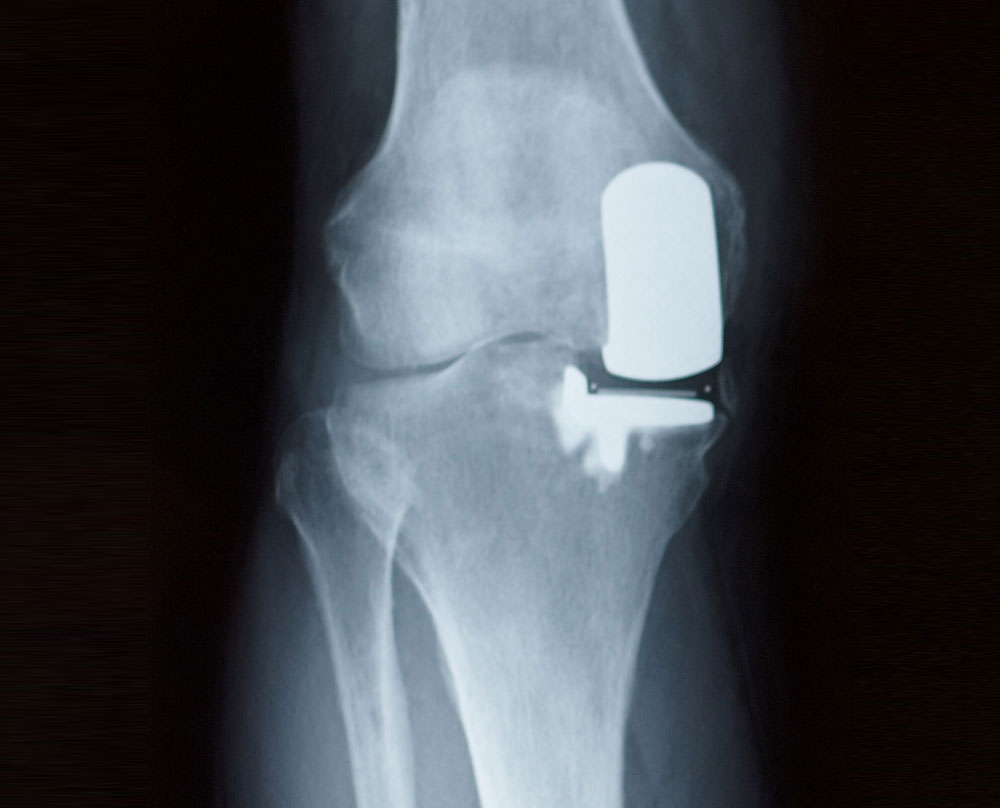

Dr. Zavoyski is a board certified fellowship trained subspecialist in total hip and total knee replacement procedures including the partial knee replacement procedure. Some patients will have damage that is located only in one specific part of the knee joint and if this is the case and they have been though other conservative measures they may be a candidate for a partial knee replacement rather than performing a total knee replacement.

The benefits of a partial knee replacement is that it is less surgery than a total knee replacement and therefore the recovery is easier for the patient. Dr. Zavoyski utilizes a robot to assist with guidance to ensure that the prosthesis is positioned appropriately.